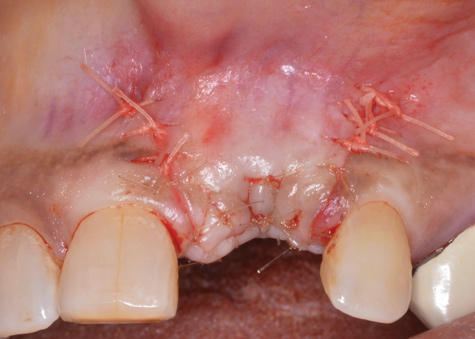

(10.) Primary, submerged closure is achieved over the newly placed implant and regenerative biomaterials.

Figure 10